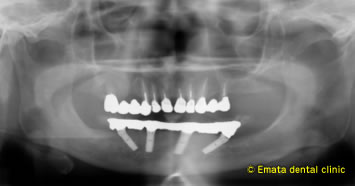

CTでシュミレーションを行いました。奥歯には骨がありませんが、前歯の骨がありますので神経までの距離が近いですが、All-on-4の適応症です。

下顎神経を避けて、4本のインプラントが綺麗に埋入されています。